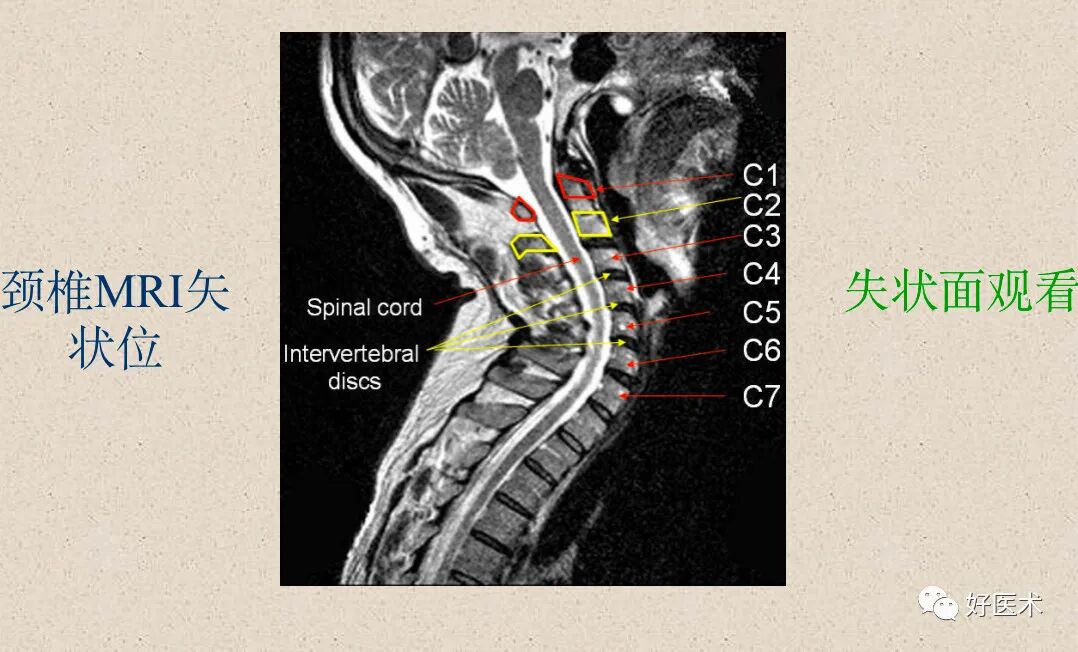

脊髓:位于椎管中心呈中等信号影

脑脊液:

T1WI上呈低信号;

T2WI上呈高信号影。

脊神经根:中等信号条状或圆点状影。

髓核:T2WI上呈较高信号

纤维环:T1WI和T2WI上均显示为低信号